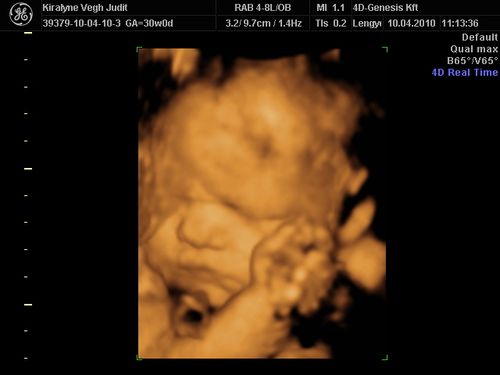

Nagyon édes a kis Izabella, tök jól sikerültek az UH képeid, nagyon fotogén a csaj!:)